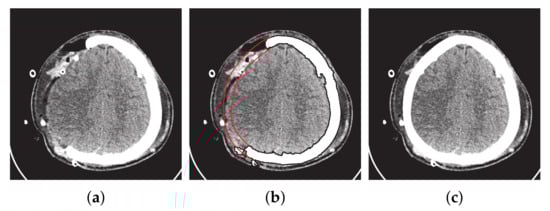

These bases are piecewise rational functions on w [ 0 , 1 ] . The authors used the NURBS curve for the construction of the parietal bone fracture on the left hand side, as shown in Figure 9.

Figure 9. Construction of fractured part using NURBS curves. (a) Original image. (b) Fractured part boundary curves reconstruction (red curves show the inner and outer boundary curves). (c) Reconstruction of fracture part into DICOM format.